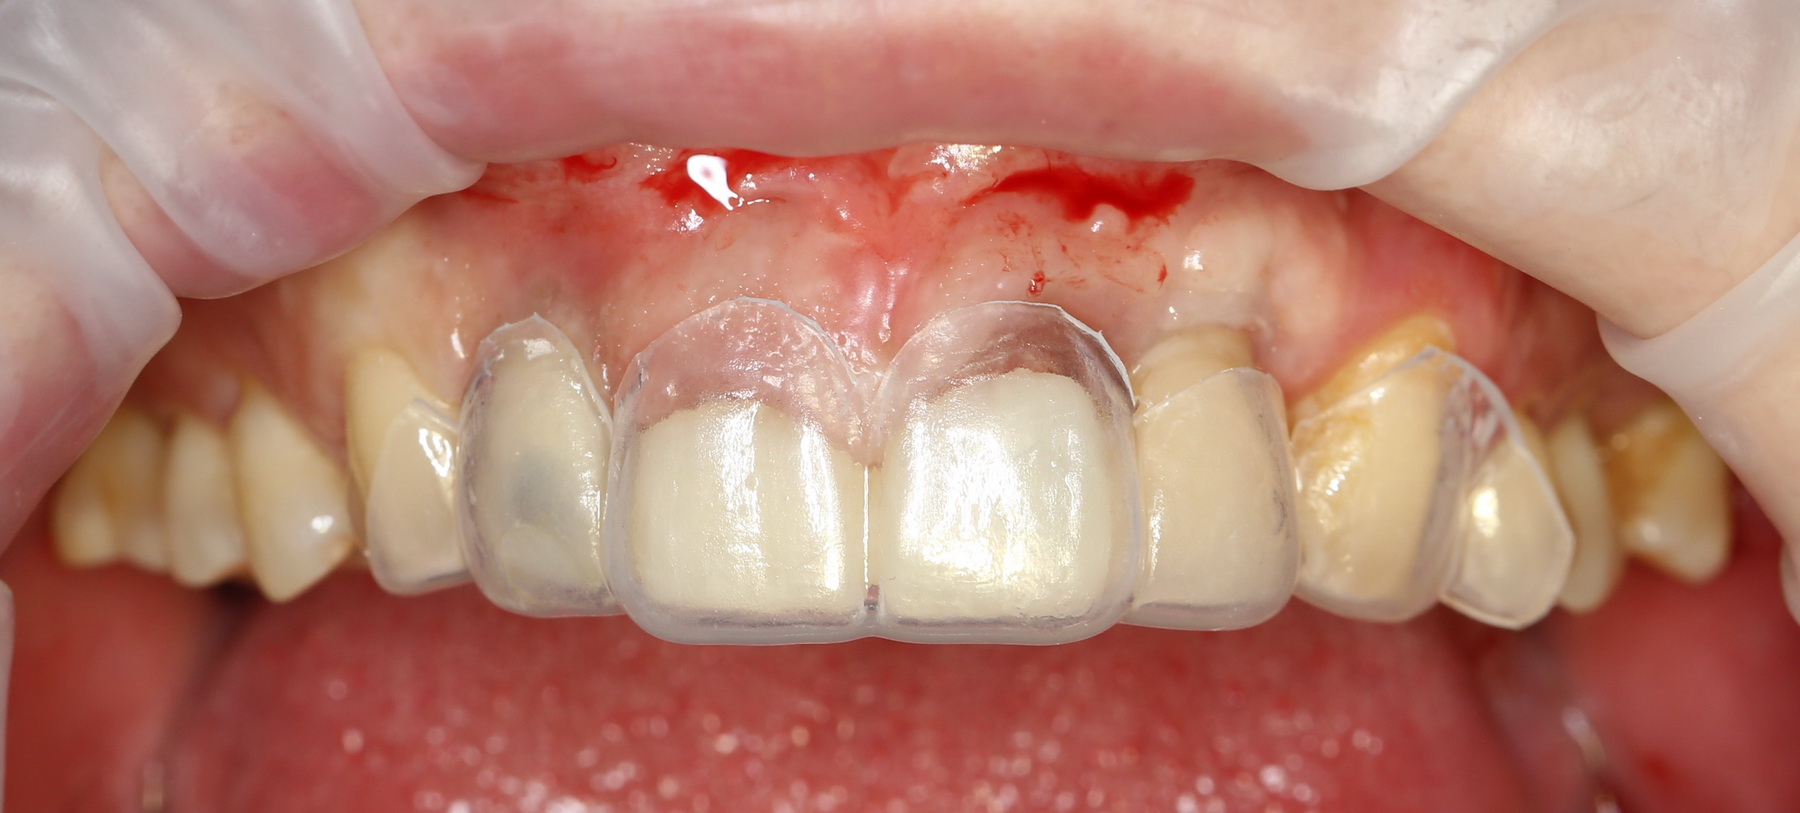

К счастью, уже через 6 недель после операции вдруг выяснилось, что ничего исправлять не нужно:

Фактически, нам осталось лишь дождаться приемлемого уровня остеоинтеграции имплантатов,  — примерно 2-3 месяца, — и можно переходить к постоянному протезированию.

Через три месяца мы сняли коронки с имплантатов, чтобы оценить качество формирования десневого контура:

С этого момента можно перестать переживать — десневой контур сформировался правильно, мы получили достаточный объём и качество окружающей платформу имплантата десны. Можно приступать к изготовлению постоянной протетики. Подрядчиком стала зуботехническая лаборатория French Creative, одна из топовых лабораторий Москвы.